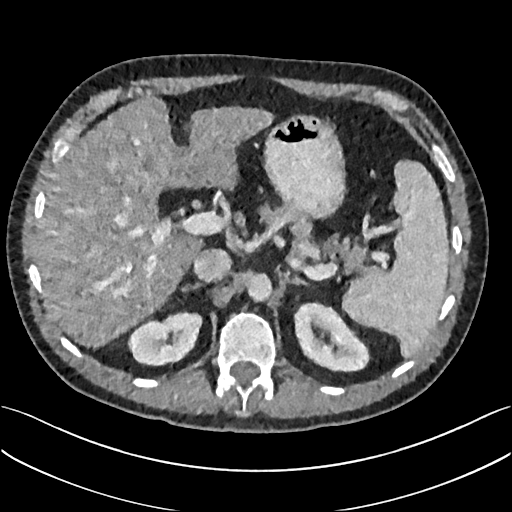

To show the denoising effect of the selected networks, we took two representative slices as shown in Figs. 5 and 7. And Figs. 6 and 8 are the zoomed regions-of-interest (ROIs) marked by the red rectangles in Figs. 5 and 7. All the networks demonstrated certain denoising capabilities. However, CNN-MSE blurred the images and introduced waxy artifacts as expected, which are easily observed in the zoomed ROIs in Figs. 6e and 8e. WGAN-MSE was able to improve the result of CNN-MSE by avoiding over-smooth but minor streak artifacts can still be observed especially compared to CNN-VGG and WGAN-VGG. Meanwhile, using WGAN or GAN alone generated stronger noise (Figs. 6g and 8g) than the other networks enhanced a few white structures in the WGAN/GAN generated images, which are originated from the low dose streak artifact in LDCT images, while on the contrary the CNN-VGG and WGAN-VGG images are visually more similar to the NDCT images. This is because the VGG loss used in CNN-VGG and WGAN-VGG is computed in a feature space that is trained previously on a very large natural image dataset [48]. By using VGG loss, we transferred the knowledge of human perception that is embedded in VGG network to CT image quality evaluation. The performance of using WGAN or GAN alone is not acceptable because it only maps the data distribution from LDCT to NDCT but does not guarantee the image content correspondence. As for the lesion detection in these two slices, all the networks enhance the lesion visibility compared to the original noisy low dose FBP images as noise is reduced by the different approaches.

As for iterative reconstruction technique, the reconstruction results depend greatly on the choices of the regularization parameters. The implemented dictionary learning reconstruction (DictRecon) result gave the most aggressive noise reduction effect compared to the network outputs as a result of strong regularization. However, it over-smoothed some fine structures. For example, in Fig. 8, the vessel pointed by the green arrow was smeared out while it is easily identifiable in NDCT as well as WGAN-VGG images. Yet, as an iterative reconstruction method, DictRecon has its advantage over post-processing method. As pointed by the red arrow in Fig 8, there is a bright spot which can be seen in DictRecon and NDCT images, but is not observable in LDCT and network processed images. Since the WGAN-VGG image is generated from LDCT image, in which this bright spot is not easily observed, it is reasonable that we do not see the bright spot in the images processed by neural networks. In other words, we do not want the network to generate structure that does not exist in the original images. In short, the proposed WGAN-VGG network is a post-processing method and information that is lost during the FBP reconstruction cannot easily be recovered, which is one limitation for all the post-processing methods. On the other hand, as an iterative reconstruction method, DictRecon algorithm generates images from raw data, which has more information than the post-processing methods.